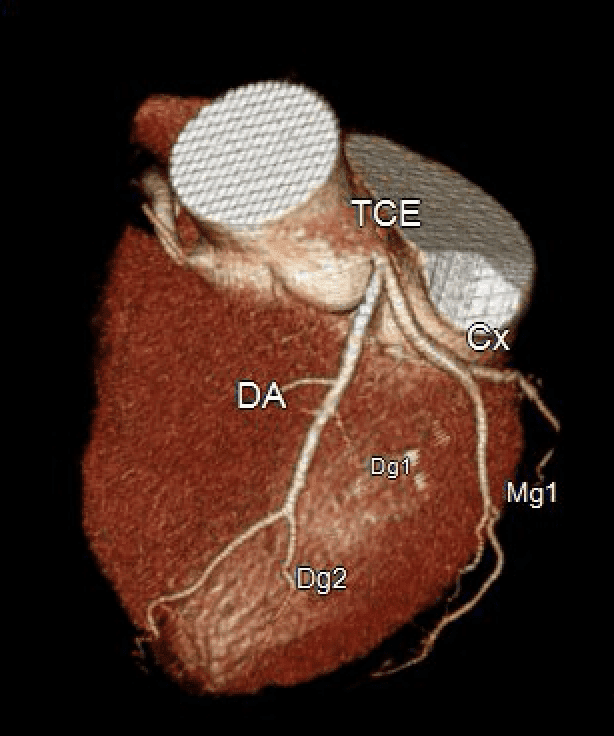

Mulher de 61 anos veio para avaliação cardiológica devido à dor torácica e dispneia aos esforços. Negava tabagismo ou doença pulmonar prévia. Achado no exame físico de sopro sistólico rude em borda es…